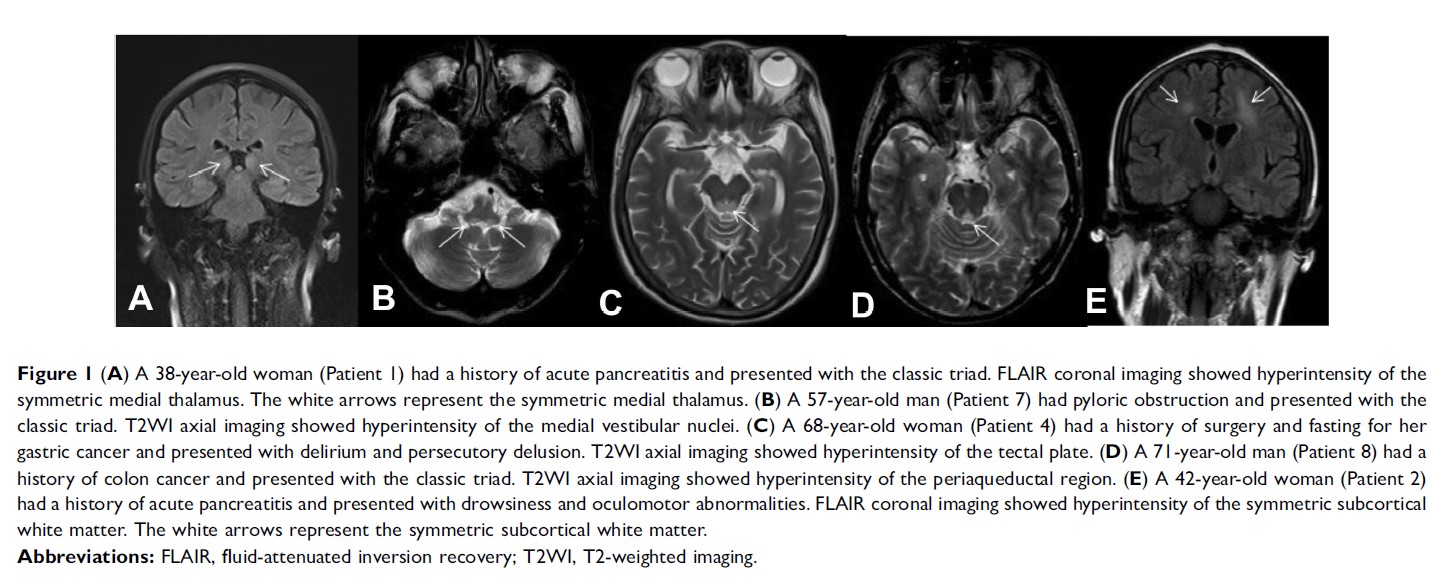

Original Research

- 作者:JinHui Liu, SiYue Li, JunYa Liang, Yi Jiang, YiCong Wan, ShuLin Zhou, WenJun Cheng

- 期刊:Cancer Management and Research